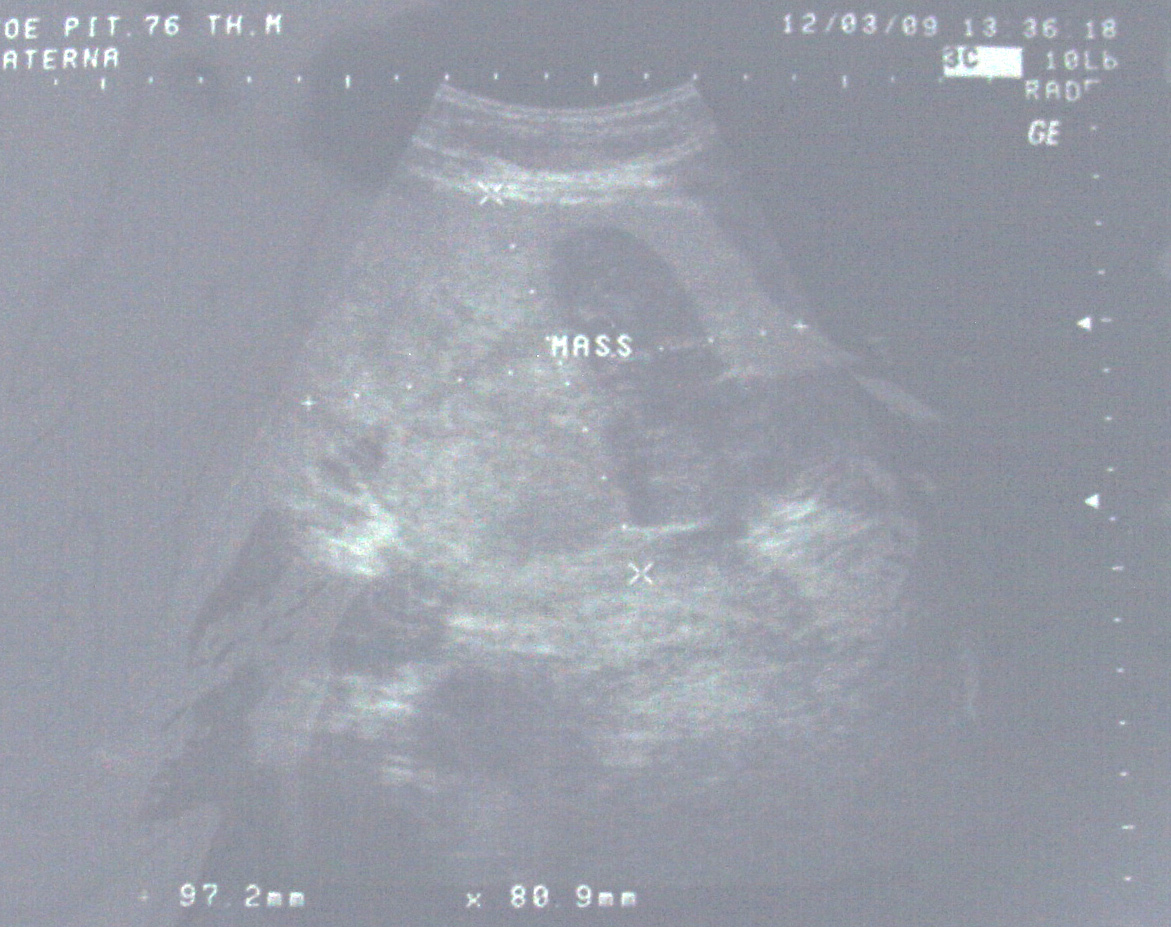

Goh adalah seorang pria berusia 75 tahun dari Indonesia. Ia menjalani pemeriksaan medis pada tahun 2008 dan dokter menemukan SGOT (AST) meninggi, mengindikasikan ada sesuatu yang tidak beres di livernya. Goh melakukan ultrasonografi dan hasilnya adalah terdapat tumor pada lobus kiri liver nya sebesar 6,3 x 8,9 cm.

Setelah kembali ke Indonesia, Goh diberitahu tentang sebuah rumah sakit di China. Goh pergi ke China. Sekali lagi dokter menyarankan untuk operasi. Dan sekali lagi dokter menyarankan untuk dioperasi. Goh menolak kembali. Bagaimanapun juga, ia setuju untuk melakukan kemoembolisasi. Ini menghabiskan biaya sekitar 10.000 RM. Setelah terapi kemo, Goh kembali ke indonesia. Sekitar satu bulan kemudian, ia kembali ke China untuk terapi kedua. Tetapi, pada saat pemeriksaan, dokter memberitahu Goh kalau kemoembolisasi yang dilakukan sebelumnya tidak efektif. Terapi lebih lanjut dibatalkan. Goh kembali ke Indonesia dan mulai mengkonsumsi suplemen. Ia juga memonitor AST nya secara reguler selain melakukan USG. Nilai AST dan ukuran tumor terus meningkat. USG yang dilakukan pada 12 Maret 2009 (dibawah) mengindikasikan tumor berukuran 9,7 cm x 8,0 cm.